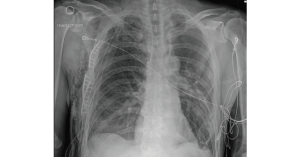

• Case Report: EMS Says Flail Chest, But Is It?